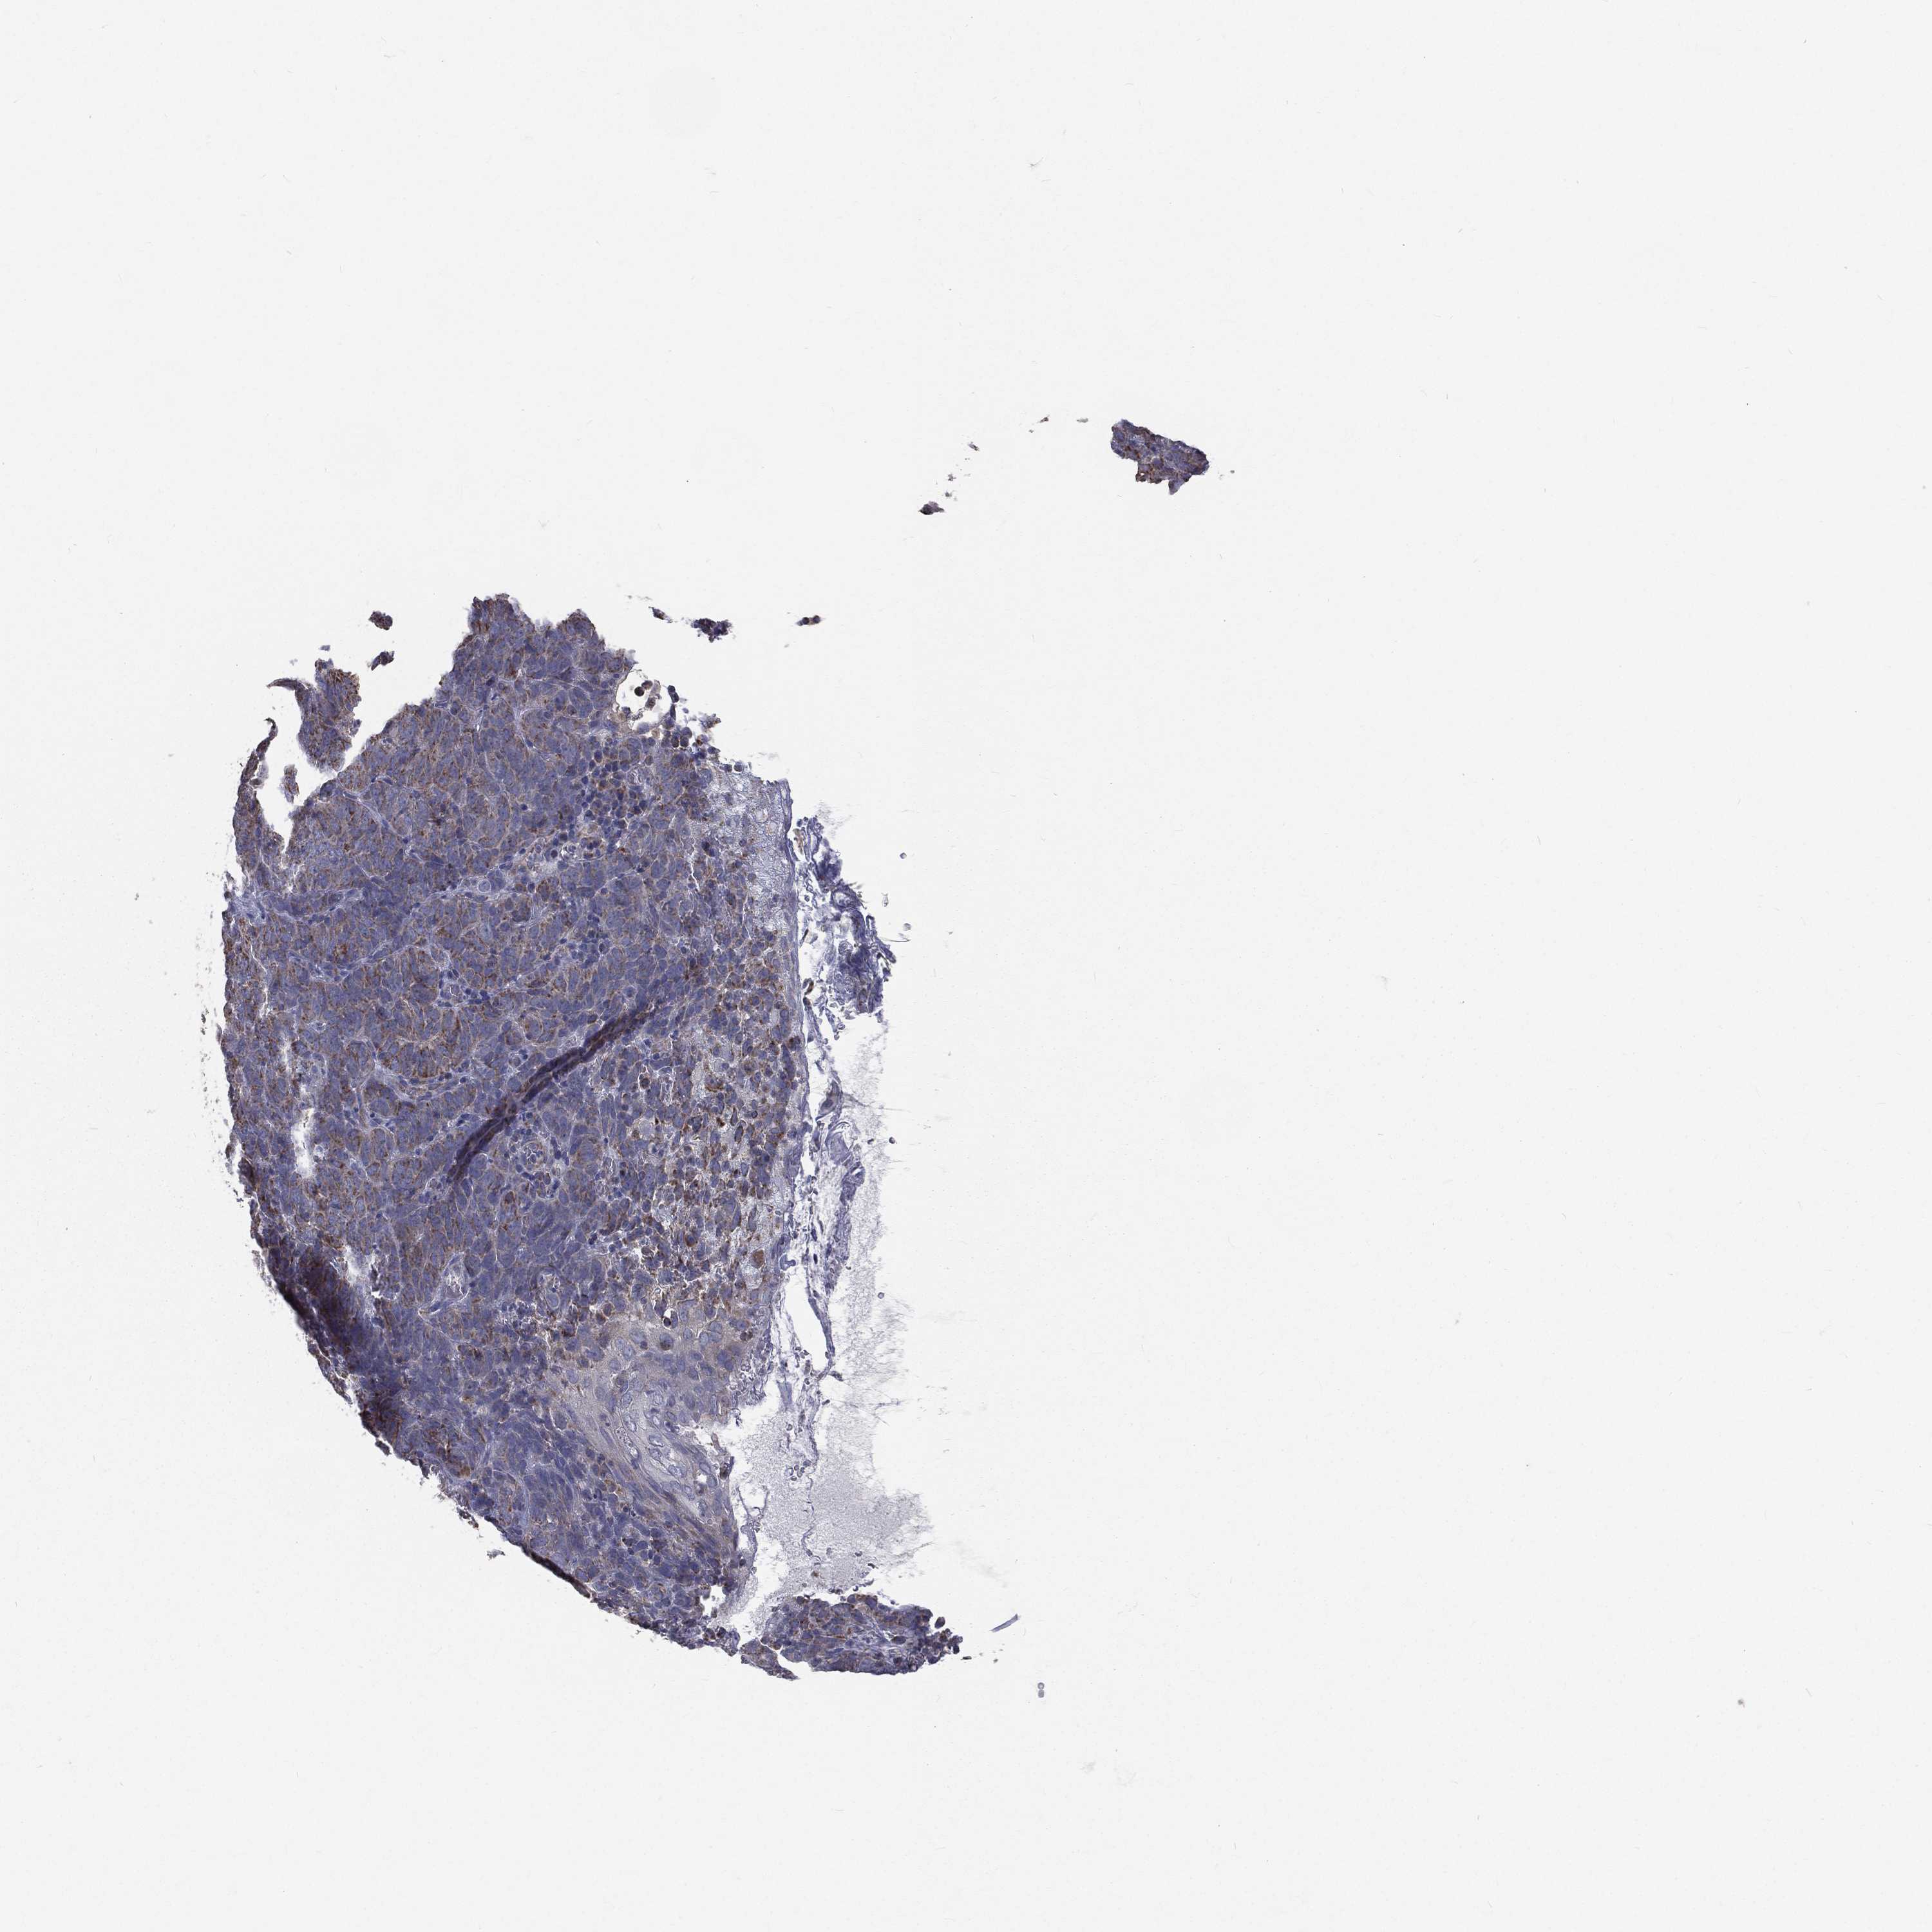

Basal cell and squamous cell cancer

SKIN CANCER - Protein expressioni

A mouse-over function shows sample information and annotation data. Click on an image to view it in a full screen mode. Samples can be filtered based on level of antibody staining by selecting one or several of the following categories: high, medium, low and not detected. The assay and annotation is described here.

Each image is clickable and will lead to virtual microscopy that enables deeper exploration of all samples and also displays staining intensity scores, fraction scores and subcellular localization as well as patient and tissue information for each sample.

Antibody HPA039588

Antibody HPA043888

Squamous cell carcinoma, NOS

Squamous cell carcinoma, metastatic, NOS